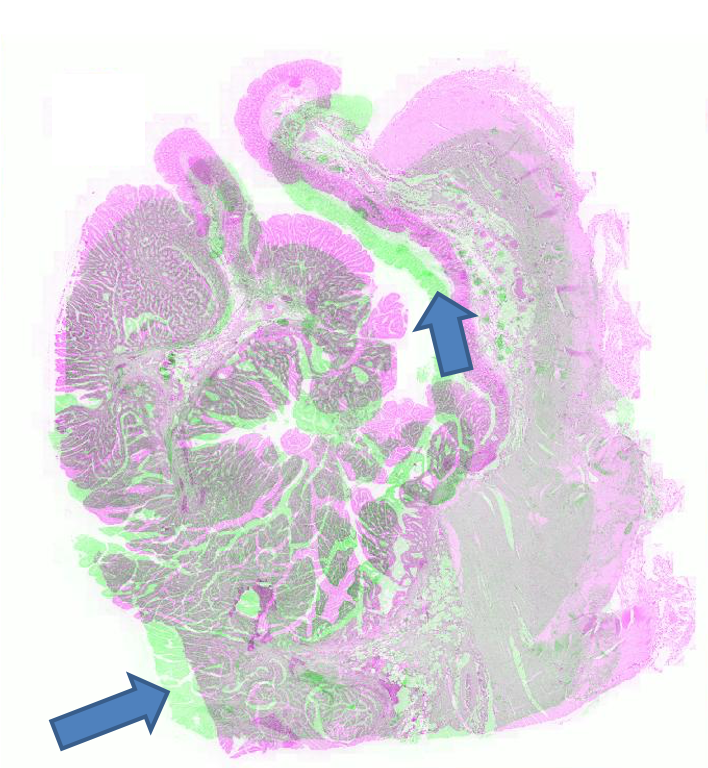

FigureΒ 2 shows the registration results for pathology images where we show the reference and floating images alongwith the misalignment images before registration and after registration using SR-Net and SR-Net. The misalignment is greatly reduced after registration using SR-Net while in the case of SR-Net there is still some resulting misalignment. This error can have significant consequences in the final diagnosis workflow. Hence the advantages of self-supervised segmentation maps are quite clear.

![]() |

| (a) | (b) | (c) | (d) | (e) |